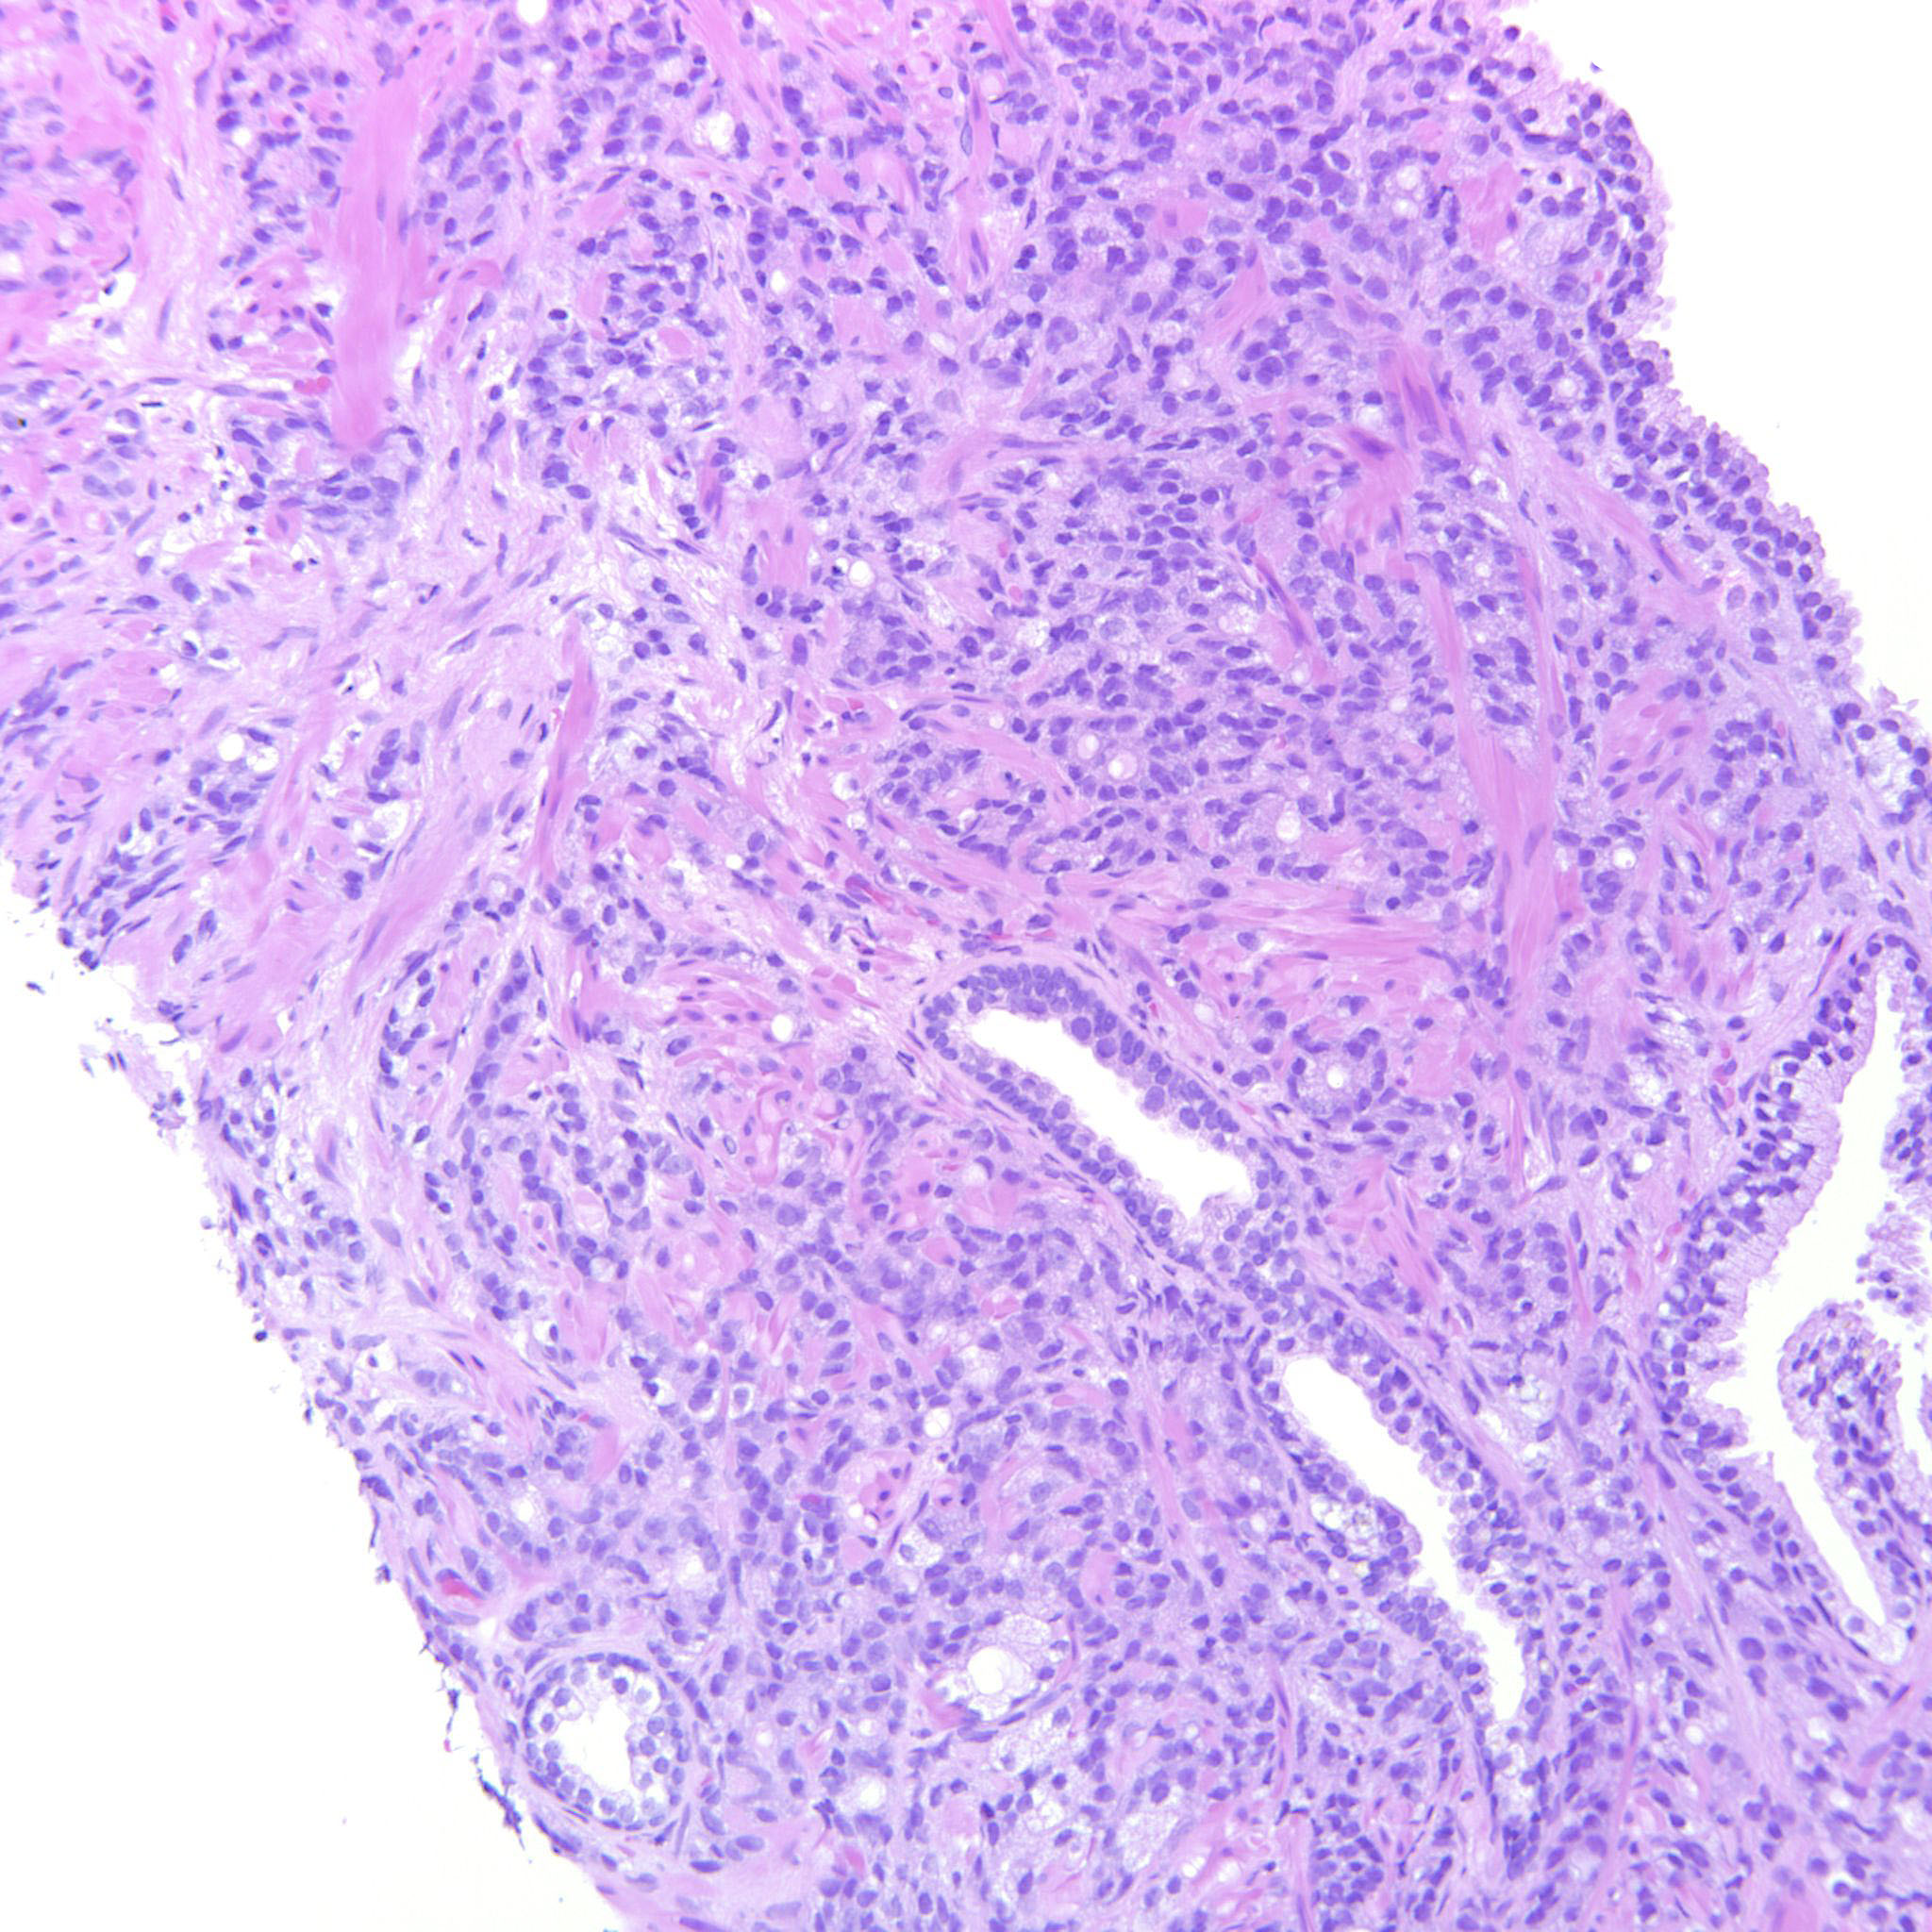

Consensus grade: GS 9-10 (ISUP 5)

Case description (by case creator):

4+5=9 where the GP5 component infiltrates diffusely in strands and single cells.